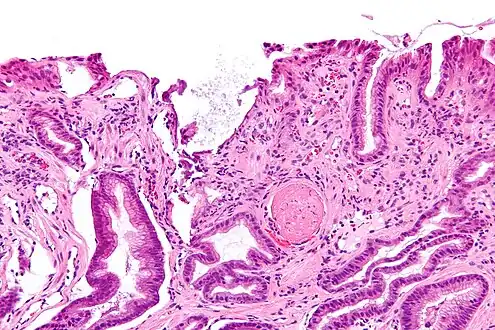

Gastric antral vascular ectasia-endoscopy

Micrograph showing gastric antral vascular ectasia. A large spherical, eosinophilic (i.e. pink) fibrin thrombus is seen off-center right. Stomach biopsy. H&E stain.

GAVE is characterized by dilated capillaries in the lamina propria with fibrin thrombi. The main histomorphologic differential diagnosis is portal hypertension, which is often apparent from clinical findings.

GAVE is usually diagnosed definitively by means of an endoscopic biopsy.[6][7][10][20] The tell-tale watermelon stripes show up during the endoscopy.[7]